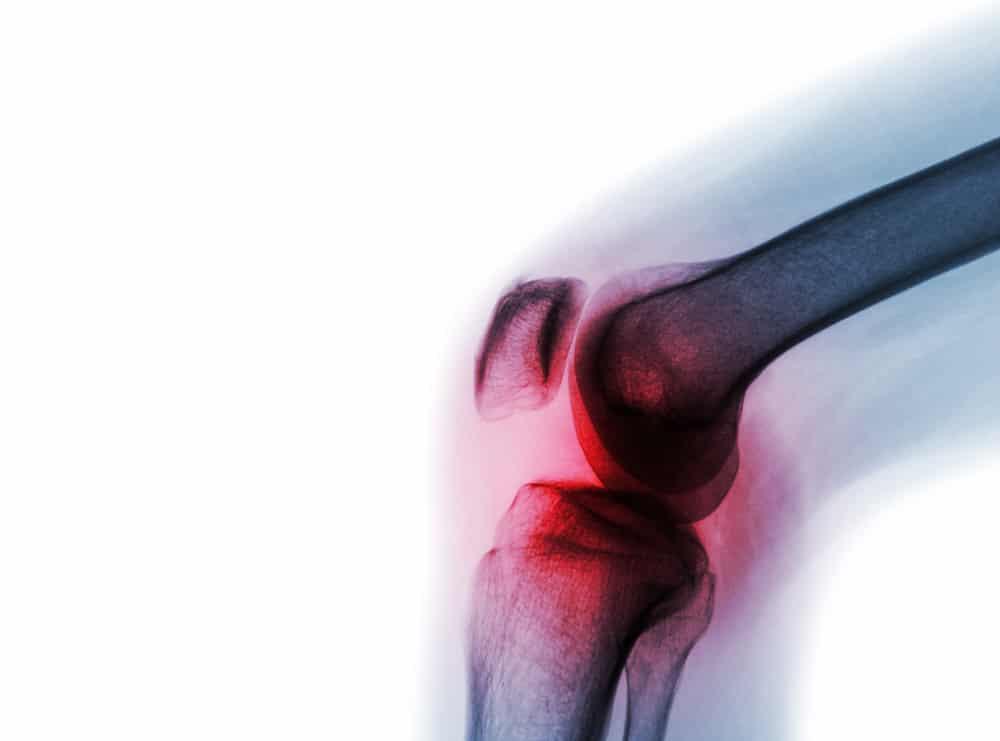

ပိုးဝင်၍ အဆစ်ရောင် ရမ်းခြင်း (septic arthritis) ဆိုတာ အရိုးအထူးကုဆရာဝန်တွေအတွက် အရေးပေါ် အခြေအနေပါ။ ချက်ချင်းကုသဖို့ သင့်တဲ့ ရောဂါပါ။ နောက်ကျသွားရင် ပိုးတွေ ပြန့်သွားပြီး သွေးဆိပ်သင့်တာ၊ အဆစ်တွေ ပျက်စီးတာ ဖြစ်တတ်ပါတယ်။ ဒါကြောင့် စောစောသိပြီး စောစောကုနိုင်ဖို့ အရေးကြီးပါတယ်။ ပိုးဝင်တာက အဆစ်တစ်ဆစ်တည်း ဖြစ်တာများပါတယ်။ ရှားရှားပါးပါး အဆစ်တွေ အများကြီး ထိတာလဲ ရှိပါတယ်။ ဒီရောဂါ ဘာကြောင့် ဖြစ်တာလဲ။ ဘယ်လို ကုသရမလဲဆိုတာ ဒီဆောင်းပါးမှာ ပြောပြပေးသွားပါမယ်။

ပိုးဝင်ပြီး အဆစ်ရောင်ရမ်းတာရဲ့ လက္ခဏာက ရုတ်တရက် နာပြီး အဆစ်တွေ ဖောင်းပြီး ရောင်လာတာပါ။ ဒါ့ပြင်

• အဆစ်က ပူပြီး နီနေတာ